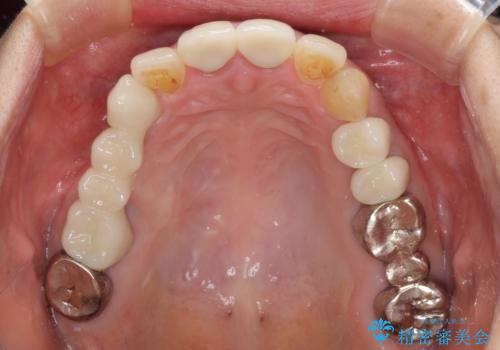

仮歯に変えた後にオールセラミッククラウンにて補綴することとしました。

治療前と比べてとても自然な前歯となり、患者様には大変満足していただきました。